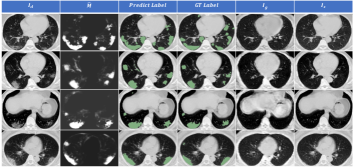

Qualitatively, visualization of the output of GASNet on four samples from the test datasets is shown in Fig. 8. The generated volume looks like a blurry version of the original input, except for the predicted lesion areas. The appearance in the predicted lesion areas changes a lot, making the generated volume look closer to a real healthy volume. Therefore, GASNet replaces the lesion areas of the original diseased volume with the corresponding parts of the generated volume, which makes the synthetic volume look quite similar to real healthy volumes. These examples show that GASNet does optimize its parameters to reach the goal of restoring original healthy CT volumes as we expect.

Refer to caption

Figure 8: The segmentation and intermediate results of GASNet of four test examples in Dataset-A. From the first column to the last column are COVID-19 CT volumes Idsubscript𝐼𝑑I_{d}, predicted segmentation masks M^^𝑀\hat{M}, predicted segmentation results, ground truth of COVID-19 CT volumes, generated CT volumes Igsubscript𝐼𝑔I_{g}, and synthesized CT volumes Issubscript𝐼𝑠I_{s}.

Figure 9: Segmentation results of three test samples in Dataset-A by three different segmentation algorithms. All algorithms used one voxel-level labeled sample for training. Idsubscript𝐼𝑑I_{d} represents COVID-19 CT volumes ; GT𝐺𝑇GT represents ground truth. The last three columns represent three different segmentation results by 3D U-Net, MIL, and GASNet. The green, yellow, and brown areas in the last three columns represent false negative, false positive, and true positive respectively. Numbers in the upper left corner represent Dice scores of current segmentation results.